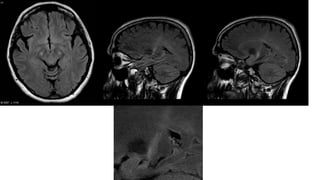

RADIOGRAPHIC FEATURES

MRI

midbrain atrophy

reduction of anteroposterior midline midbrain diameter, at the level of

the superior colliculi on axial imaging (from interpeduncular fossa, to

the intercolicular groove: <12mm 8): which can give a mickey mouse

appearance

reduced area of the midbrain on midline sagittal and reduced midbrain

to pons area ratio: approx 0.12 (normal approx 0.24) on midline

sagittal

Loss of the lateral convex margin of the tegmentum of midbrain has

been described as the morning glory sign

hummingbird sign also known as the penguin sign. The key is a

flattening or concave outline to the superior aspect of the midbrain

which should be upwardly convex

•T2: diffuse high-signal lesions in

• pontine tegmentum

• tectum of the midbrain

• inferior olivary nucleus